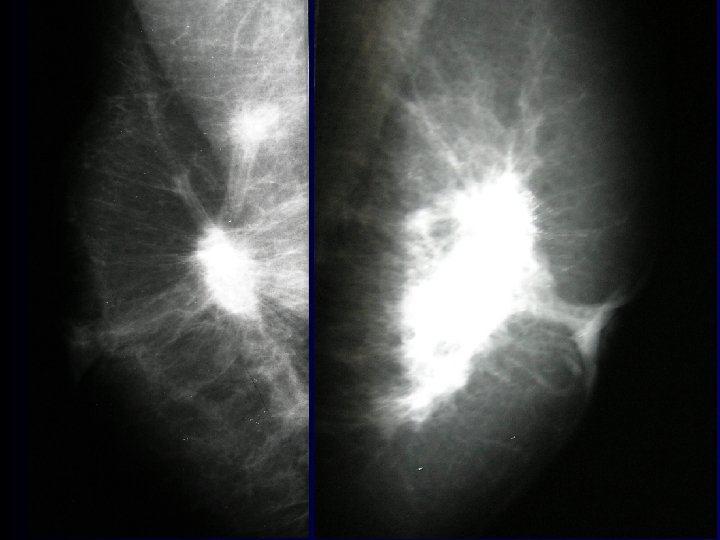

Carcinoma of breast • most frequent tumor in females Afflicts 9% of female population • clinical signs – bulging, skin/areolar invagination, ulceration • examination – palpation, ultrasound, mammography, lymph nodes • exstirpation Pictures – 1. LF UK

Adipose mamma Coopers ligaments

Average glandular mamma